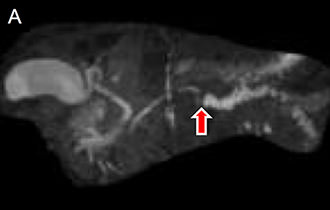

図5 膵体尾部切除と術後化学療法を行った膵癌症例

膵体部に主膵管の閉塞を伴う膵癌を認めました(矢印)。リンパ節郭清を伴う膵体尾部切除と術後化学療法を行い、約8年間無再発生存中です。

• A.MRIによる膵管造影

• B.内視鏡エコーによる膵腫瘤像